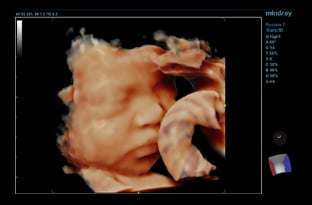

Volume Ultrasound Transducer

A volume transducer is a specialty transducer that captures 3D/4D images and can be utilized in a variety of applications. They can be useful in helping clinicians to appreciate depth better and achieve a more realistic representation of anatomy in additional planes. Volume transducers are typically used for cardiac and OB/GYN imaging.

Baby face visualized with volume transducer